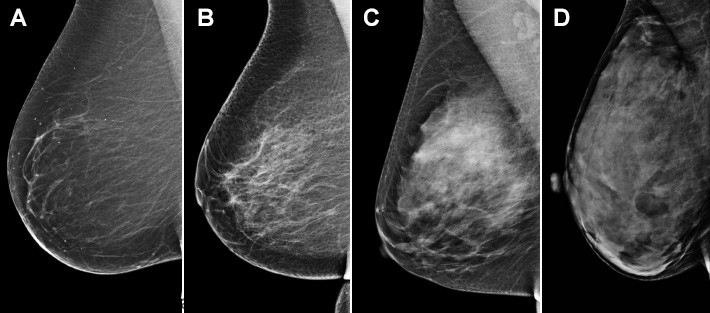

بافت متراکم سینه فقط در ماموگرافی قابل مشاهده است. در حالی که بافت چربی در ماموگرافی تیره به نظر می رسد، بافت متراکم سفید به نظر می رسد. برای حدود نیمی از زنان، ماموگرافی غربالگری نشان میدهد که بافت سینهشان متراکم است.

الف) عمدتاً چرب: سینه ها عمدتاً از بافت چربی تشکیل شده و دارای بافت فیبری و غده ای بسیار کمی است. حدود 10 درصد از زنان سینه های چرب دارند.

ب) تراکم فیبروگلندولار پراکنده: سینه ها عمدتاً بافت چربی هستند، اما در ماموگرافی چند ناحیه از بافت فیبری و غده ای قابل مشاهده است. حدود 40 درصد از زنان دارای تراکم پراکنده هستند.

ج) متراکم ناهمگن: در ماموگرافی مناطق زیادی از بافت فیبری و غده ای نشان داده می شود. حدود 40 درصد از زنان این نتیجه را دریافت می کنند.

د) بسیار متراکم: سینه ها دارای مقادیر زیادی بافت فیبری و غده ای هستند. حدود 10 درصد از زنان در این دسته قرار می گیرند.

زنان با نمره C یا D به عنوان سینه های متراکم طبقه بندی می شوند. رادیولوژیست طبقه بندی را انجام می دهد، بنابراین اغلب نیاز به قضاوت دارد - و مطالعات نشان می دهد که دو رادیولوژیست ممکن است یک زن را متفاوت طبقه بندی کنند. به همین دلیل، اکنون بسیاری از مراکز تصویربرداری سینه از نرم افزار خودکار برای کمک به ارزیابی تراکم سینه استفاده می کنند.

سینه های متراکم تشخیص سرطان سینه را برای رادیولوژیست ها هنگام خواندن ماموگرافی دشوارتر می کند. سرطان ها معمولاً به صورت لکه های کوچک سفید یا توده هایی در ماموگرافی ظاهر می شوند. بافت متراکم پستان نیز در ماموگرافی سفید به نظر می رسد. نواحی کوچک سرطان می توانند پشت بافت متراکم پنهان شوند و تشخیص تفاوت بین بافت طبیعی و سالم و رشد غیرطبیعی چالش برانگیز است. سازمان DenseBreast-info.org آن را با "تلاش برای دیدن یک آدم برفی در کولاک" مقایسه می کند. بافت چربی سینه در ماموگرافی تیره به نظر می رسد، بنابراین مناطق نگران کننده ای که سفید نشان می دهند بسیار راحت تر دیده می شوند.

افزایش تراکم سینه (چربی تیره و بافت سینه سفید است)

تراکم سینه به دو دلیل مهم است. اول، تشخیص سرطان سینه در ماموگرافی در بافت متراکم پستان دشوارتر است. دوم، زنانی که بافت سینه متراکمی دارند، نسبت به زنانی که سینههای چرب دارند، کمی بیشتر در معرض ابتلا به سرطان هستند. میانگین تراکم یک زن در ایالات متحده بین پراکنده و ناهمگن است و 80 درصد از زنان در این دو دسته متوسط قرار می گیرند.